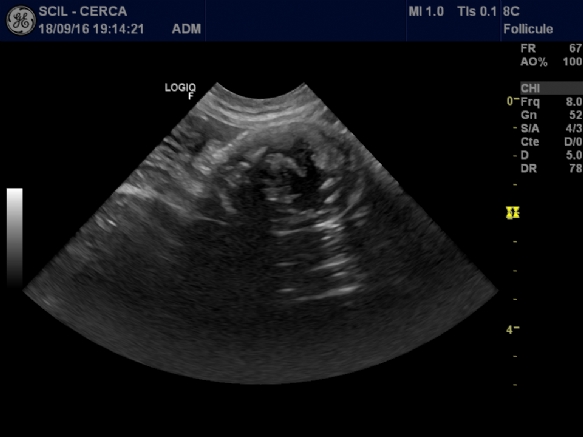

Photos 1 Images échographiques en différentes coupes de la masse abdominale. Structure sphérique sans lien apparent avec les organes aux alentours. Quelques cônes d'ombre sont observés attestant de la présence de zones calcifiées.

- échographie abdominale (photos n° 1) : observation d'une masse sphérique hétérogène de 2 cm de diamètre avec des parties calcifiées ; aucun lien avec les organes autour n'a été identifié, la masse semble encapsulée ; certaines zones semblant calcifiées, il a été décidé de réaliser une radiographie abdominale ;